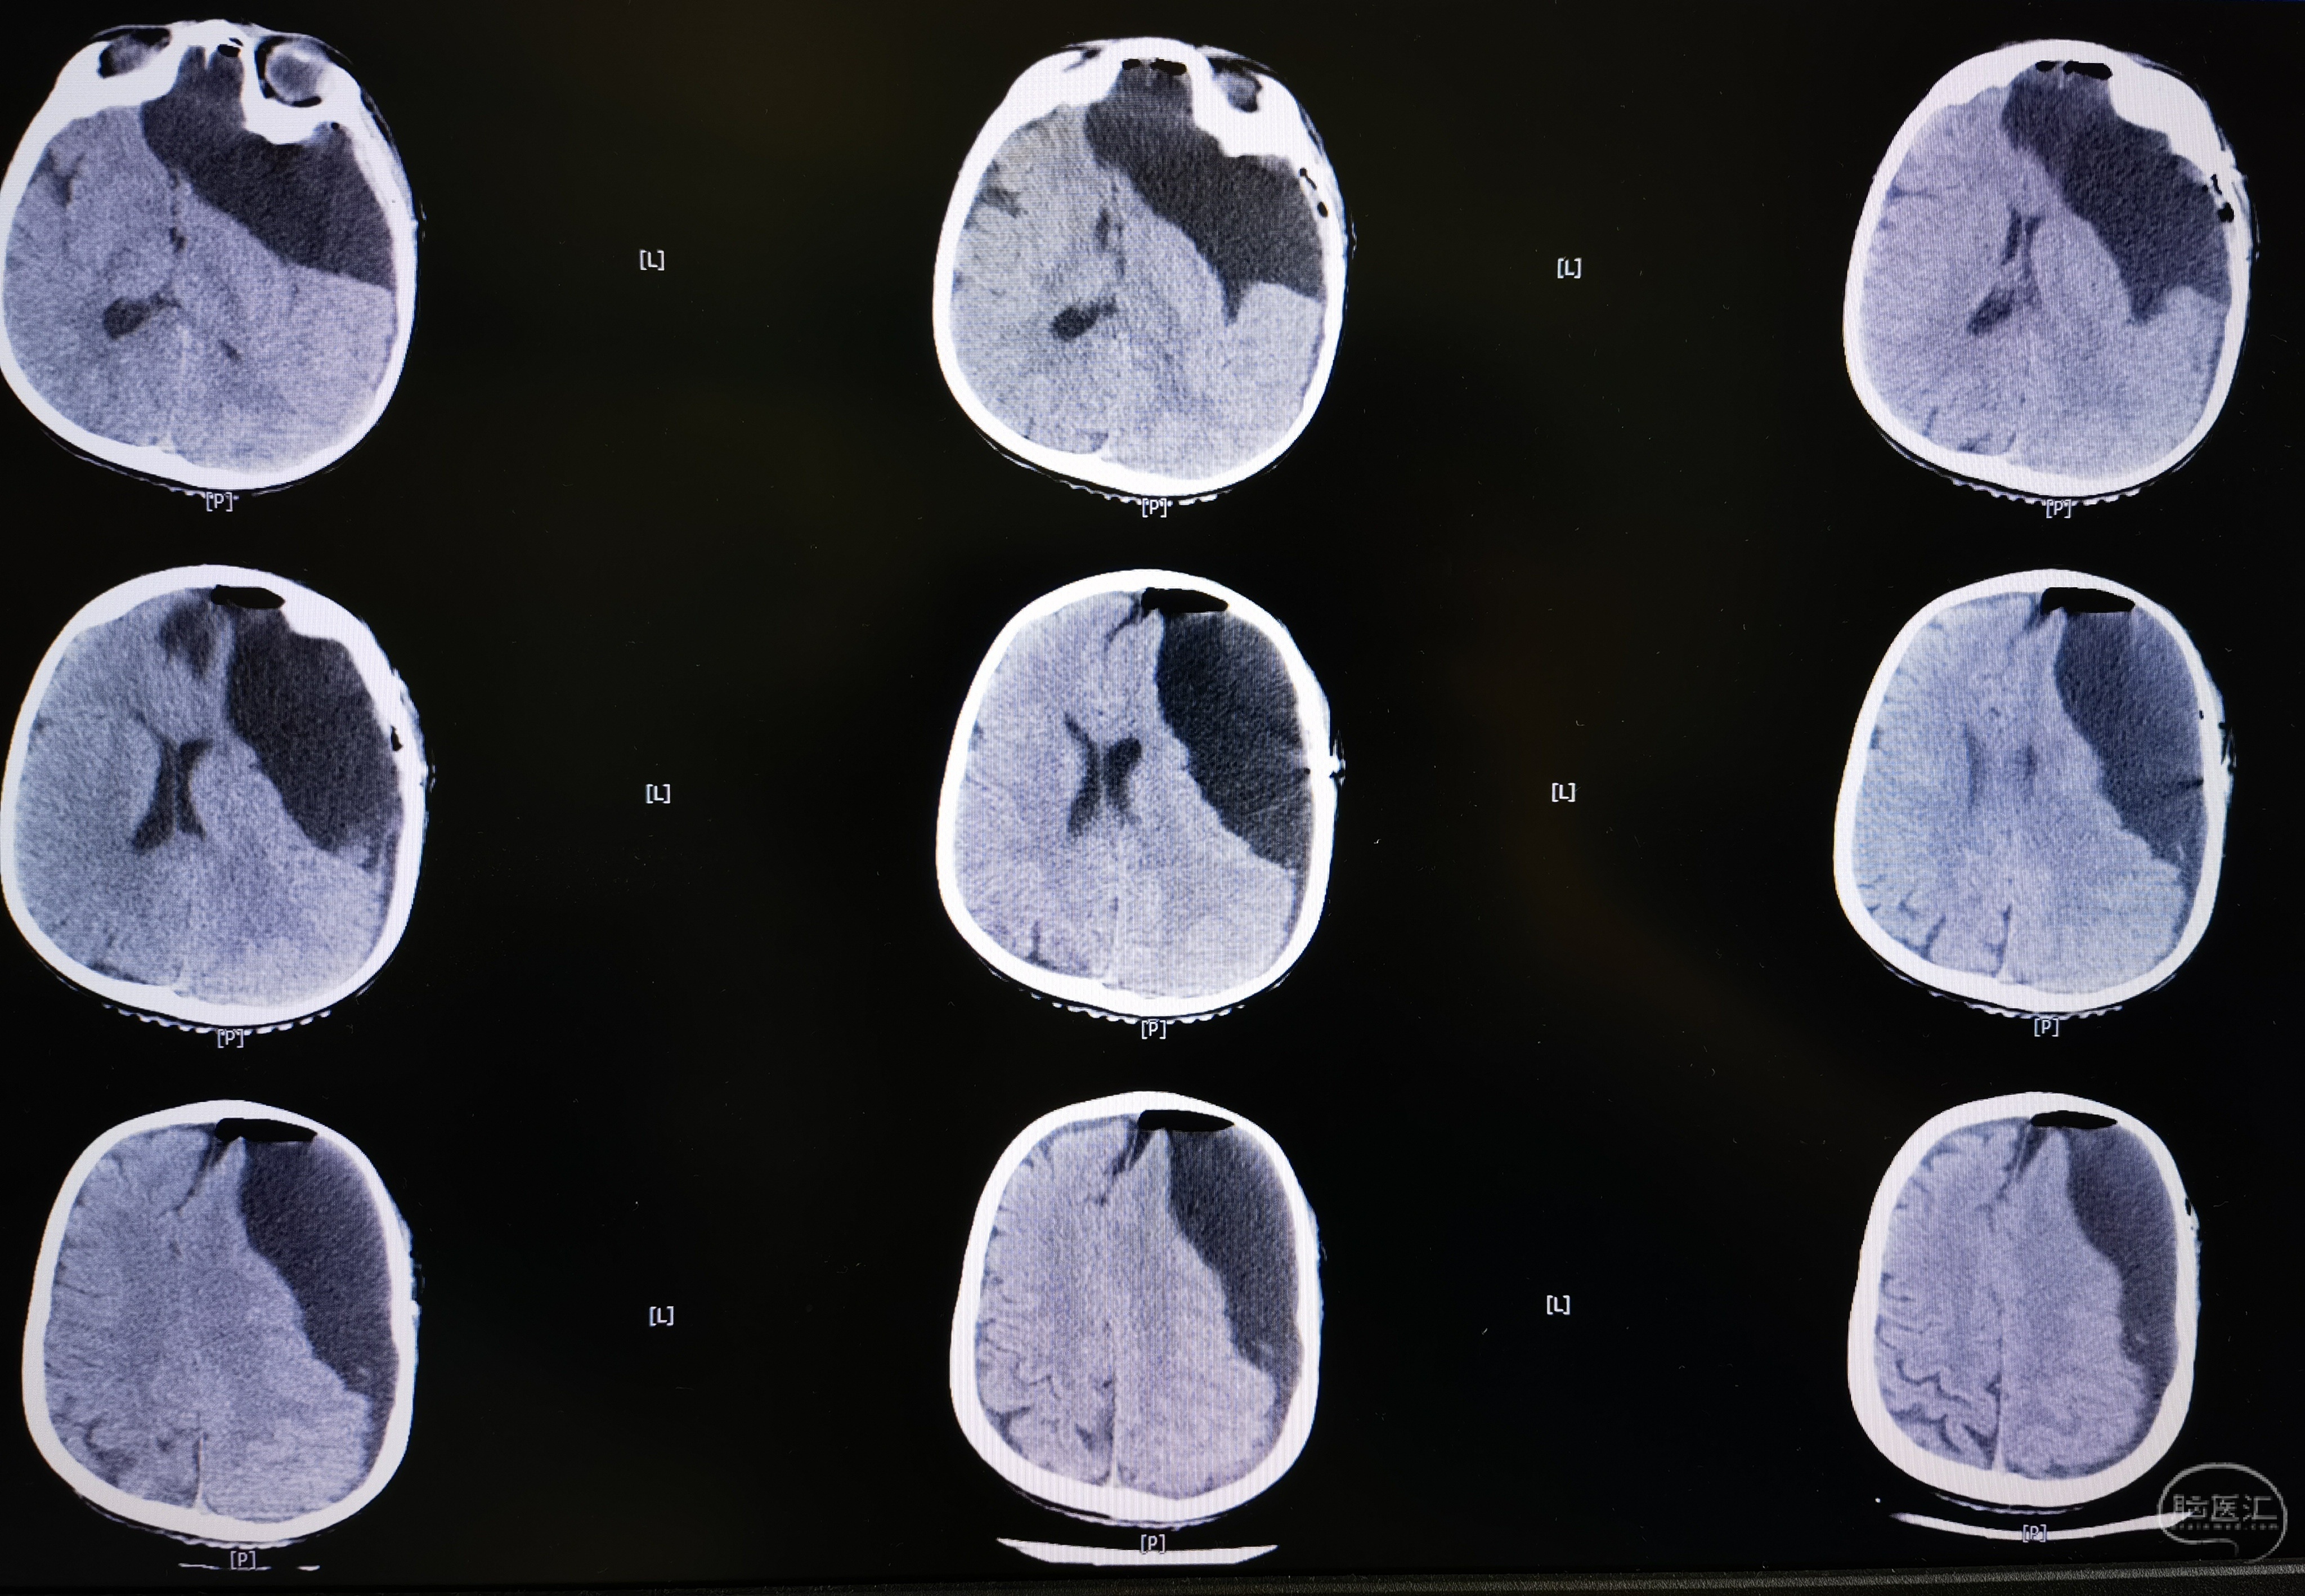

术后CT